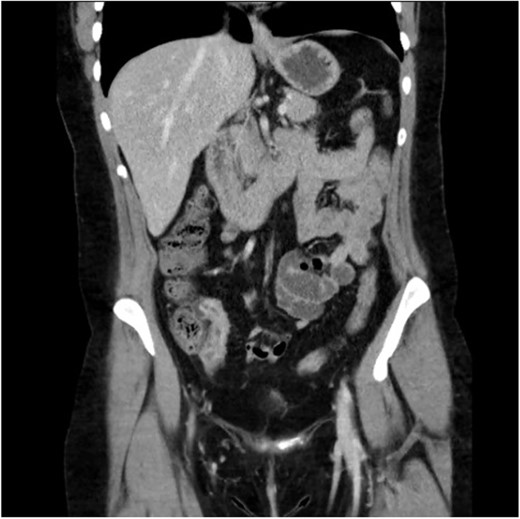

A 34-year-old female presented with colicky episodic abdominal pain and symptoms suggestive of subacute small bowel obstruction in the setting of known stricturing CD. Her symptoms were poorly controlled on multiple medications—Azathioprine, Mesalazine, Adalimumab and Budesonide. She had no previous history of abdominal surgery or gynaecological pathology. She had twice undergone endoscopic balloon dilatation of a terminal ileal stricture with short-lived symptomatic relief. Contrast-enhanced computed tomography (CT) of the abdomen and pelvis showed a short segment of acute inflammation of the terminal ileum (Fig. 1) and an incidental right adnexal cyst. Pelvic ultrasonography was normal. Magnetic resonance enterography confirmed stricturing CD with two segments of inflammation of the terminal ileum (lengths of 5 and 3.8 cm) approximately 5 cm from the ileocaecal valve (Fig. 2).

Computed tomography scan (portal venous phase post intravenous contrast) showing a short segment of thickened, enhancing terminal ileum consistent with terminal ileitis of CD.